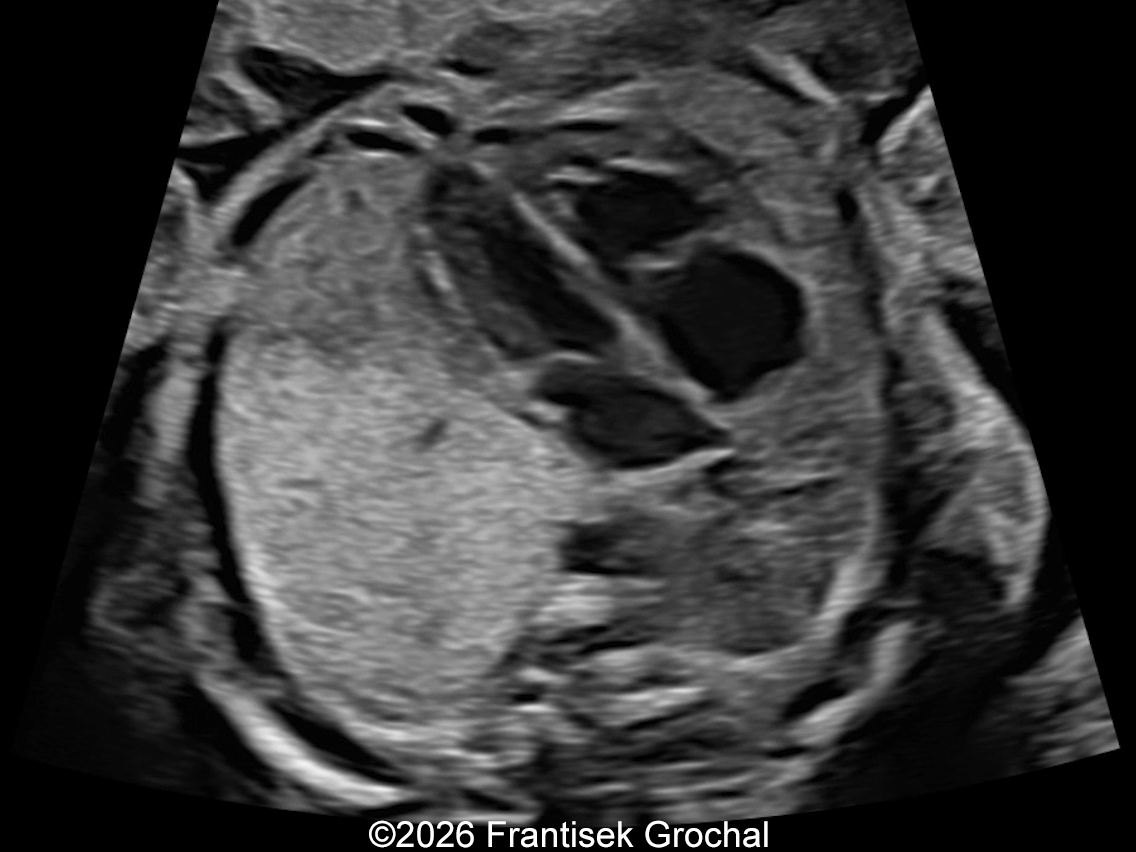

31+4 weeks – transverse thoracic view showing normal cardiac position; the pulmonary sequestration is barely discernible.

Image 5 31+4 weeks – transverse thoracic view showing normal cardiac position; the pulmonary sequestration is barely discernible.